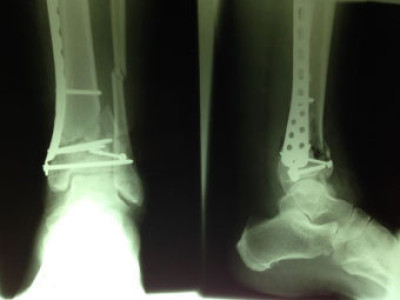

Fractura de Tibia Distal